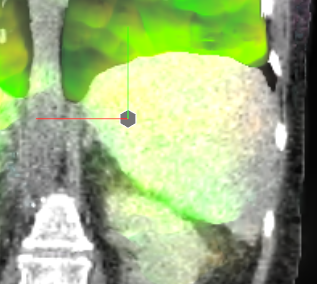

Figure 4: Coronal views with overlayed motion field to the CT data of the patient pat3D𝑝𝑎𝑡3𝐷pat3D (a-d) deformed with the model of pat4D𝑝𝑎𝑡4𝐷pat4D. The color wheel legend below indicates the direction of the motion field.

The mean DICE coefficients of the single-atlas registration of the liver and lung masks to the new static patient pat3D𝑝𝑎𝑡3𝐷pat3D yield satisfying values of 0.86±plus-or-minus\pm0.12 and 0.96±plus-or-minus\pm0.09. Note the clearly different scan ranges of the data sets (Fig. 2a). The animation of the relevant structures is shown as an example in Fig. 3, using a variable real breathing signal of the target patient pat3D𝑝𝑎𝑡3𝐷pat3D (Fig. 2b). In the puncture-relevant liver region, the patient’s breathing states are simulated plausibly for the 4D reference patient (Fig. 3) and, more importantly, the 3D patient (Figs. 4, 5), to which the motion model of pat4D𝑝𝑎𝑡4𝐷pat4D was transferred333Demo movie, click here.

We achieve qualitatively plausible results for the liver area in this feasibility study. In the upper thorax especially at the rib cage in neighborhood to the dark lungs stronger artifacts can occur (Fig. 5c). They are due to problems in the inter-patient registration that is a necessary step for the transfer of the motion model. The non-linear deformation sometimes is prone to misaligned ribs. The same is true for the lower thorax with perforation first of the liver and then diaphragm (Fig. 4c). Further optimization have to be carried out as artifacts can appear on the high contrast lung edge (diaphragm, ribs) with a small tidal volume. For liver punctures only, the artifacts of smeared ribs are minor as can be seen in Fig. 4.